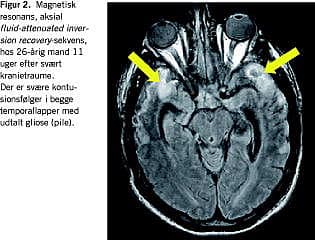

Såkaldte T2 *-vægtede sekvenser har høj sensitivitet for hæmoglobinderivater og er derfor specielt egnede til detektion af blødninger. Petekkiale blødninger ledsagende DAI bliver herved synlige [3] (Figur 1 ). Alligevel tillader T2 *-vægtning kun visualisering af et mindretal af DAI-læsioner, idet man fra autopsistudier ved at mere end 80% af DAI-læsioner er nonhæmoragiske. Antallet af synlige DAI-læsioner på T2 *-vægtede billeder er da heller ikke nogen god prognostisk markør. Punktformede hypointensiteter ved prædilektionssteder for DAI, dvs. subkortikal hvid substans, corpus callosum og dorsolaterale mesencefalon er ikke desto mindre indikativt for tilstedeværelse af en svær primær diffus hjerneskade.